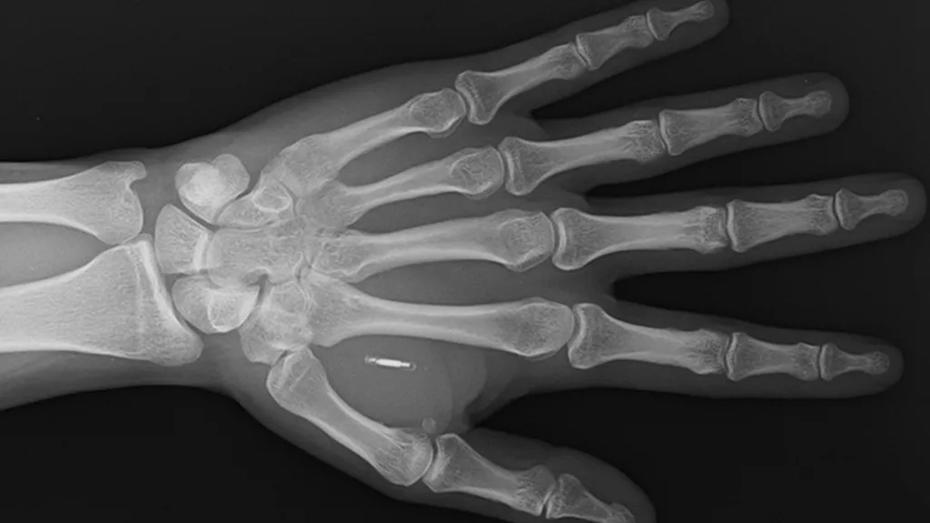

ABD’nin Missouri eyaletinde yaşayan sihirbaz ve moleküler biyolog Zi Teng Wang, eğlenceli bir deneyim için eline yerleştirdiği mikroçipin şifresini unuttu. Bu durum, Wang’ı kendi bedenine yerleştirdiği teknolojiye erişemeyen bir birey haline getirdi. Wang, Facebook’ta yaşadığı bu ilginç durumu aktarırken, çipin yerini gösteren bir röntgen görüntüsünü de paylaştı.

“Zi the Mentalist” sahne adıyla bilinen Wang, bu çipi yıllar önce çeşitli sihir numaralarında kullanmak için eline yerleştirmişti. Ancak, seyircilerin telefonlarını çipin yanına yaklaştırması, sihir numaralarının beklediği kadar gizemli bir hava yaratmadı. Wang, bu deneyimin ilginç olmadığını ve çoğu kişinin RFID okuyucusunun devre dışı kaldığını belirtti.